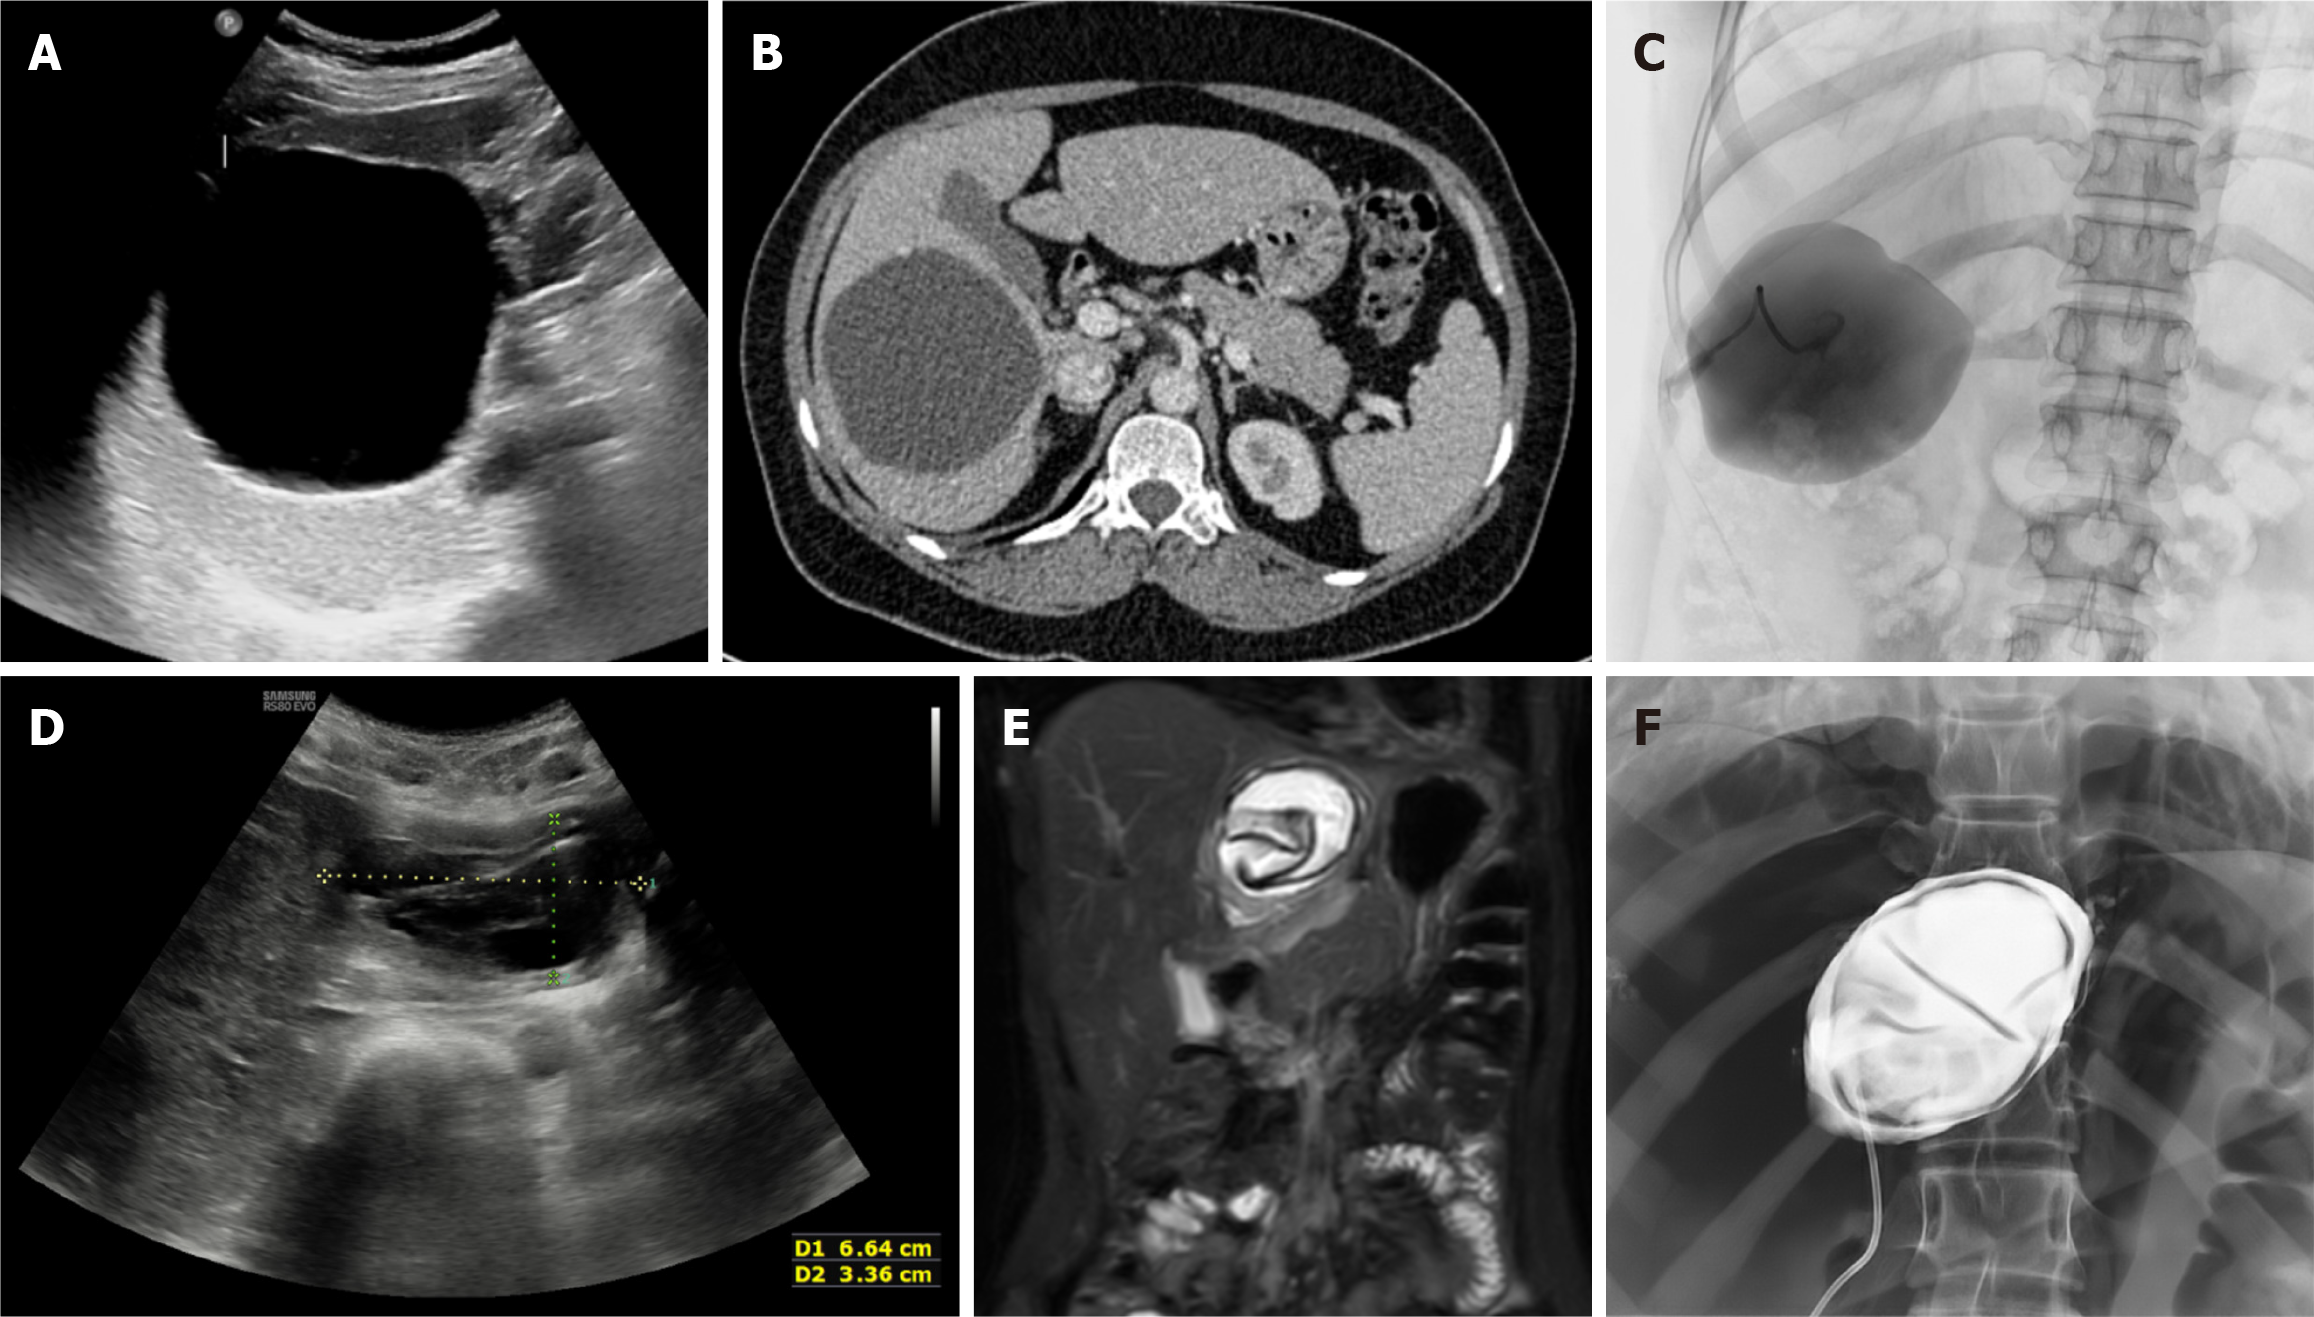

Figure 5 Puncture-aspiration-injection-reaspiration procedure. A-C: Ultrasound (A) and axial computed tomography image (B) depict a cystic echinococcus 1 hydatid cyst in the right lobe of the liver. Fluoroscopic spot image (C) shows opacification of the cyst cavity following contrast injection, confirming correct intracystic placement with no evidence of cysto-biliary communication; D-F: Axial ultrasound (D) and coronal T2-weighted magnetic resonance imaging image (E) in a different patient depicts a cystic echinococcus 3a hydatid cyst in the left lobe of the liver. Fluoroscopic spot image (F) obtained during the puncture-aspiration-injection-reaspiration procedure shows opacification of the cyst cavity, with the floating membranes visualized as curvilinear filling defects, with no evidence of cysto-biliary communication.

MoCAT

This technique is utilized for uncomplicated CE2 and CE3b HHC[10], which have significant solid components (Figure 7), that cannot be removed by PAIR. It aims to remove the entire parasite-derived cyst components (the parasitic larval wall, germinal layer, and the cyst contents comprising fluid, brood capsules, protoscolices, and breakdown products) and utilizes larger bore catheters (12F-16F depending on fluid viscosity). It is currently performed at limited centres, and larger clinical trials are needed to explore MoCAT, as it has the potential to replace surgery for the cyst types not amenable to PAIR.

The initial step is puncture of the HHC with an 18-G needle, followed by instillation of contrast (cavitography) to rule out cysto-biliary communication. Then, over a 0.035 inch stiff guidewire, a large-bore catheter is inserted via Seldinger’s technique (manipulation with the wire and catheter also helps in destroying daughter cysts). Isotonic saline (0.9%) is then injected into the cyst with immediate reaspiration. This leads to aspiration of the pieces of membranes along with the fluid content. This step is repeated multiple times (> 100 times, if necessary) until there is complete cavity evacuation (also referred to as “effective and aggressive irrigation of the cavity”)[24]. The catheter may need to be repositioned within the cyst under US/fluoroscopic guidance to better evacuate the cyst’s contents. Multiple sessions may be required, if necessary. After complete evacuation of the cyst contents, and repeat injection of contrast (to rule out cysto-biliary communication and ensure complete emptying of the cyst cavity), scolicidal agent is instilled (hypertonic saline followed by 95% ethanol) followed by its reaspiration. When there is complete cyst collapse and the daily drainage is < 10 mL, the catheter can be removed. In case there is persistent daily drainage of > 10 mL for 10-14 days after the procedure, patients can be referred for endoscopic papillotomy/common bile duct stenting to reduce the biliary pressure, and achieve rapid closure of any cysto biliary fistula formed during the previous steps of this procedure.

MoCAT has a lower recurrence rate as compared to PAIR and S-CAT; however, has a higher rate of complications such as cysto-biliary fistula development and abscess formation[24]. T2-weighted MRI, in addition to US, plays a crucial role in minimizing recurrence by helping confirm complete clearance of cyst contents and the germinal layer[10]. In the study by Akhan et al[43], patients undergoing MoCAT (for CE2 and CE3b) had a mean hospital stay of 3.88 ± 4.73 days, with 89.9% patients discharged within the first week. Major complications occurred in 9.09% cases, with recurrence occurring in 4.5% cases.

This technique is a modification of the PAIR technique, and can be employed for CE1, CE2, CE3a, and CE3b HHC (Figure 8)[45]. The first step is puncture of the HHC using a 22-G needle, which is in contrast to the 18G needle used in PAIR, leading to a reduced risk of cyst fluid leakage and secondary peritoneal hydatidosis[45]. Multiple punctures can be performed in the same session (up to 5), especially for CE2 and CE3b cysts, to achieve better distribution of the sclerosing agent. The volume of fluid aspirated is 3 times the largest dimension of the HHC (3 cm3 for every 1 cm), which equates to ≤ 2 % of the total cyst volume[45]. This is much less than the 20% fluid aspirated in PAIR. Because of this, there is less reduction of the intracystic pressure, which may not fall below the normal intrabiliary pressure, thereby reducing the chances of development of cysto-biliary communication. The next step is injection via the puncture needle of equal volume of the aspirated fluid with 95% ethanol (2/3 volume) and 1% polidocanol (1/3 volume), which is kept in situ for 5 minutes. The advantage of polidocanol is that it enhances the sclerosing effect of ethanol, and it obstructs small communications with the biliary and venous system, if present. Catheters are not used, which reduces the chances of infection and shortens hospital stay. The scolicidal agent is not re-aspirated, which increases the scolicidal effect. Very limited evidence, largely derived from small case series and observational studies, suggests that the Örmeci technique may be associated with higher clinical success and lower morbidity, mortality, and recurrence rates compared with PAIR[46]. However, these findings are preliminary, and larger studies are required to validate their efficacy and safety.

Figure 8

Figure 8 Örmeci technique. A: Axial computed tomography image shows a hydatid cyst in the right lobe of the liver; B: Fluoroscopic spot image during Örmeci procedure: Contrast is injected through the puncture needle, which fills the cyst cavity with no opacification of biliary radicles, ruling out cysto-biliary communication; C: Ultrasound image depicting puncture needle in situ within the hydatid cyst.